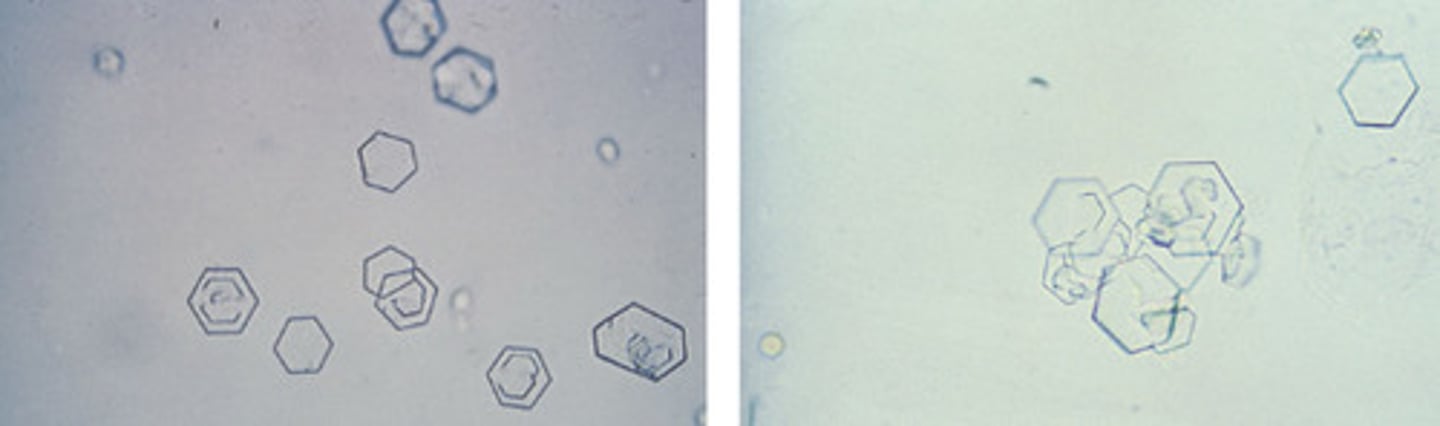

Triple Phosphate